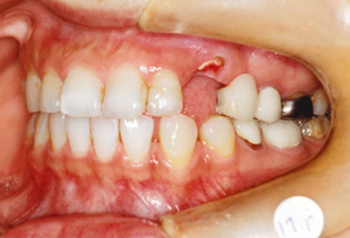

主訴:上顎左側3番を残して欲しい

診断名:上顎左側3番歯肉カリエスにより挺出を行い、上顎左側③4⑤⑥番ブリッジを装着

症状:歯ぎしりがある

患者プロフィール:北九州市小倉北区30代女性

治療方針:上顎左側3番歯肉縁下カリエスにより挺出を行い、上顎左側③4⑤⑥番ブリッジを装着する

治療装置:白い表側矯正装置(マルチブラケット)

抜歯:非抜歯

治療期間:約6か月

説明したリスク副作用:痛み・治療後の後戻り・歯根吸収・歯髄壊死など